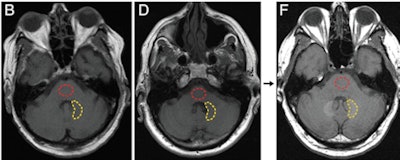

Axial T1-weighted MR images show the posterior fossa at the level of the dentate nucleus. Image B is of a control group patient, while image D is the first MRI exam and F is the last MRI exam of a patient in the contrast group. Regions of interest used to quantify signal intensity are shown as dashed lines for the dentate nucleus (yellow) and pons (red). Images courtesy of Radiology.McDonald told AuntMinnie.com that the Mayo team decided to investigate the issue after a 2013 paper by Kanda et al found a connection between gadolinium contrast and brain abnormalities in some patients. The Mayo Clinic was well-suited for the research as it performs most of the autopsies done in southeastern Minnesota, and it also has long-term records on contrast administration for its patients, McDonald said.